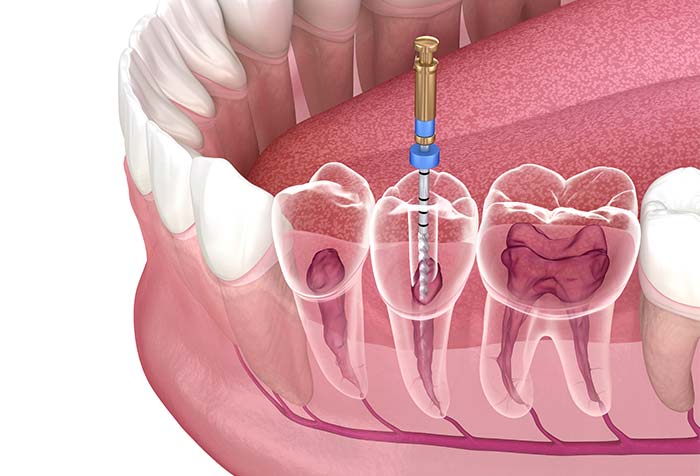

根管治療

根管治療とは、歯の根の部分を治す治療です。むし歯が進行すると感染が歯の根まで及び、炎症や強い痛みを引き起こします。その場合、感染した組織を取り除き、根管の内部を殺菌して薬を詰め、密閉することで無菌に近い状態にします。こうした処置により、歯を抜かずに残せることもあります。なお、難しい症例については根管治療を専門とする歯科医師が在籍している歯科医院をご紹介しています。